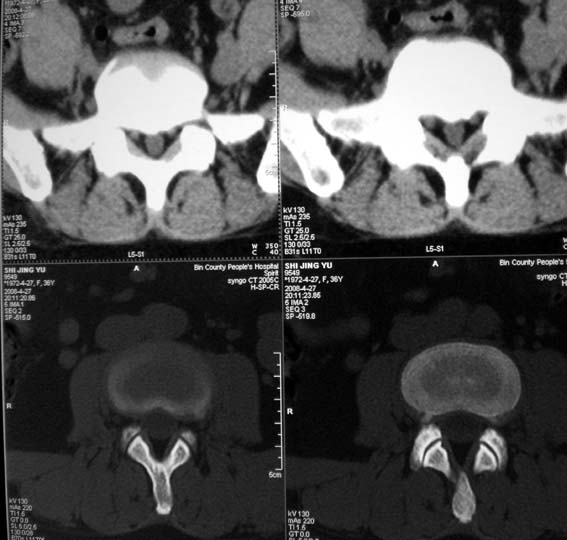

女,36岁,腰痛多年,坐久后,起身疼痛难忍。

腰4/5椎间盘轻度膨出,腰5/骶1椎间盘突出(右旁中央型)伴局部椎间盘钙化。

腰4~5椎间盘轻度膨出,腰5~骶1椎间盘突出(右侧型)伴局部椎间盘钙化。

后纵韧带钙化。